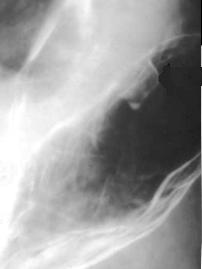

Image une tumeur

epithelial begnin de estoma . Aspect polipoide a

sessile intraluminale |

Image TOGD d'une tumeur epitheliale a la

region antrale de l'estomac .Sa surface est

irregulier lobulaire |